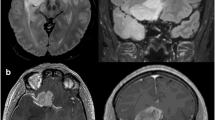

Illustrative cases

Representative cases are shown in Figs. 4 and 5.

This is the case of a 40-year-old woman, right handed, with no medical antecedent, KPS 90. She presented with insular seizures (somatosensitive and digestive symptoms). The preoperative MRI reported a probable right fronto-temporo-insular low-grade glioma (no contrast enhancement). She underwent a preoperative functional MRI with speech area activation showing only left side activation. The preoperative volume was 42.8 cm3. The surgery was performed with two IoMRI followed by additional resection. The EOR was 91% with a tumor residue < 4 cm3. The histological result reported an astrocytoma WHO grade II. No postoperative deficit was noted